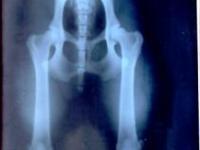

DISPLASIA DE CADERA

Clasificación grado de displasia